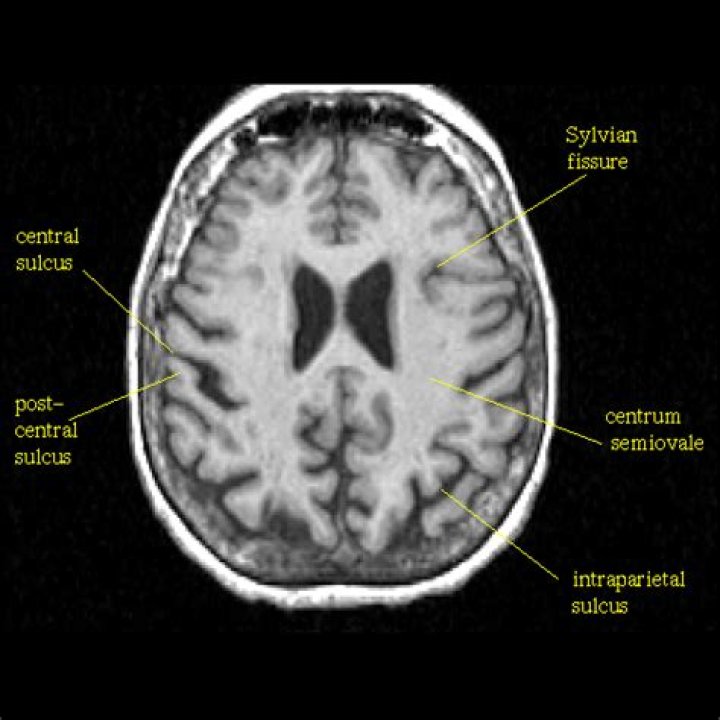

The centrum semiovale (plural: centra semiovale) is a paired mass of white matter superior to the lateral ventricles and corpus callosum, present in each of the cerebral hemispheres, subjacent to the cerebral cortex. It has a semi-oval shape and contains projection, commissural, and association fibers.

The corona radiata refer to a pair of white matter tracts seen at the level of the lateral ventricles. Superiorly they are continuous with the centrum semiovale. Inferiorly these tracts converge as the internal capsule.